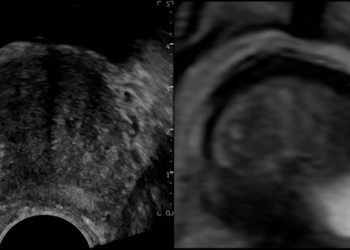

El diagnóstico definitivo de cáncer de próstata se obtiene mediante el analisis histopatológico del tejido extraído en una biopsia. La biopsia transrectal guiada por ultrasonido, técnica ampliamente utilizada desde la década de los 80`s es la mas conocida, sin embargo en la última década se han desarrollado nuevas técnicas con el objetivo de aumentar su precisión diagnóstica, una de estas es la biopsia prostática con fusión resonancia magnética-ultrasonido (MRI-TRUS) que permite sincronizar las imágenes obtenidas por resonancia magnética con las imágenes generadas por ultrasonido en tiempo real y dirigir la toma de muestras hacia las zonas de sospecha.